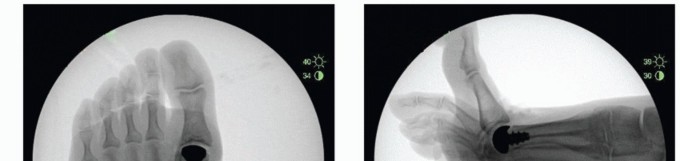

Obtain final AP and lateral fluoroscopic images to confirm alignment of the HemiCAP DF device. A maximally dorsiflexed lateral view may also be obtained (TECH FIG 9).

- TECH FIG 9 • Intraoperative fluoroscopic views following HemiCAP DF resurfacing. A. AP view. B. Lateral view neutral. C. Lateral view dorsiflexion.